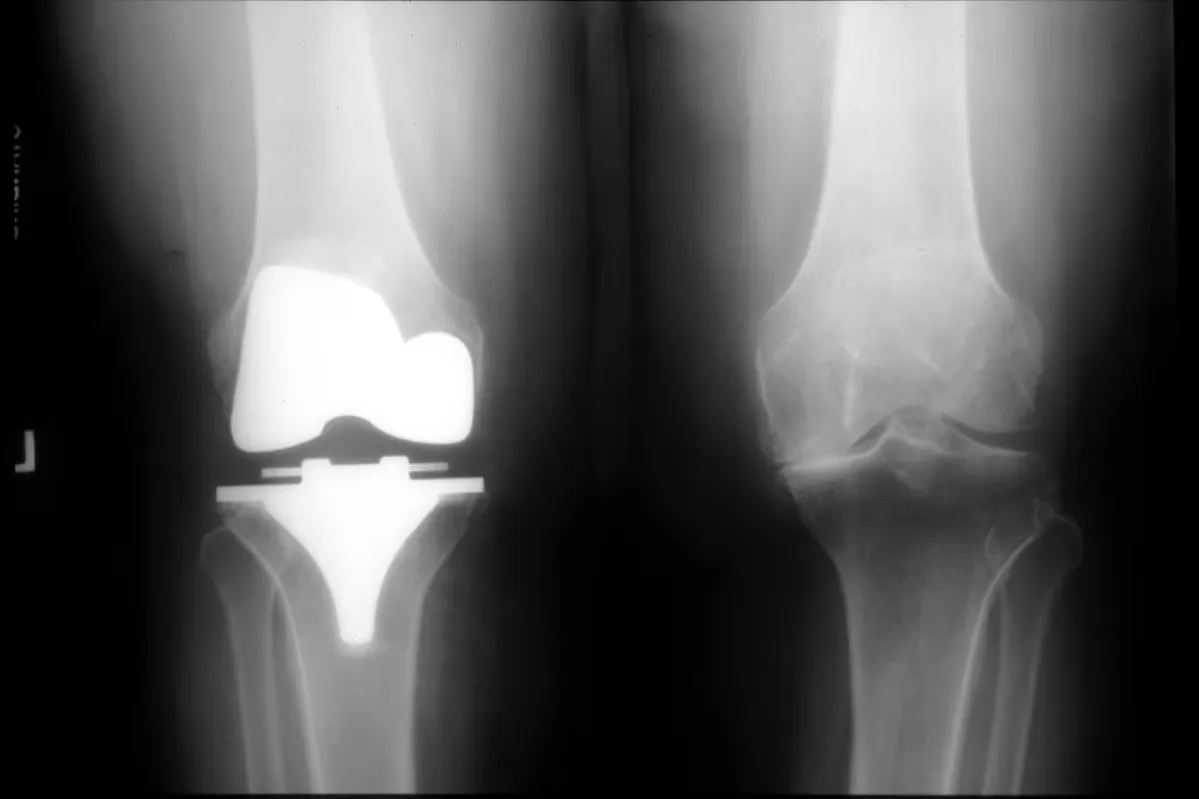

Arthroplasty is performed if all other modalities are ineffective and osteotomy is not appropriate or if a patient cannot perform ADLs despite maximal therapy. This procedure alleviates pain and may improve function. At a minimum, 10-15 years of viability are expected from joint replacement in the absence of complications.